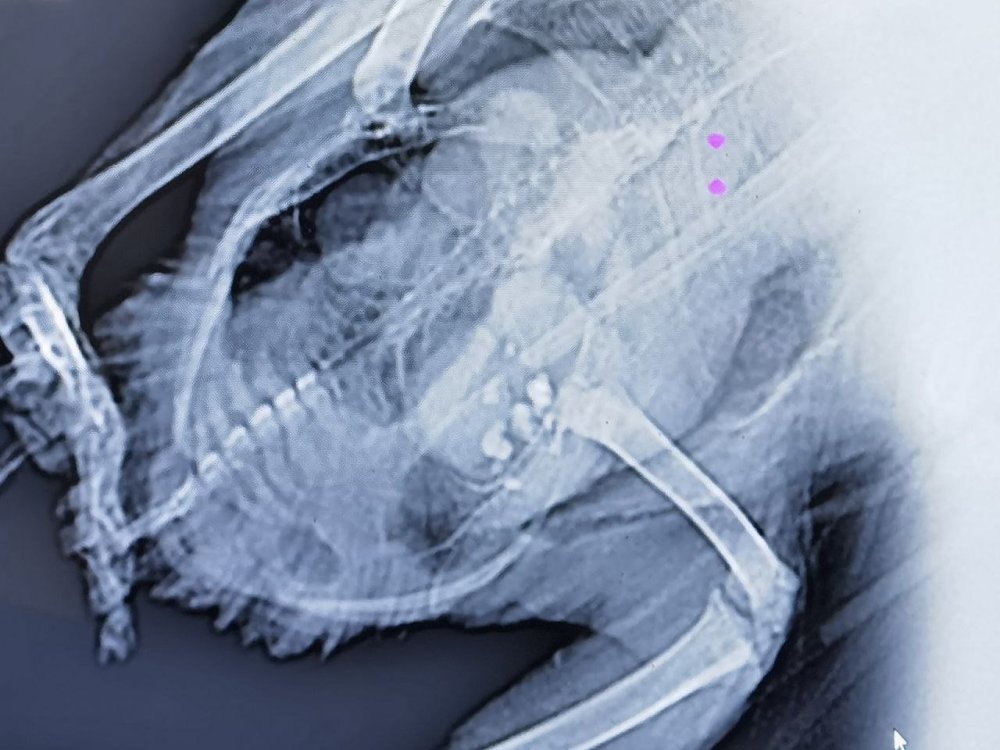

@Budgiek @свс @Cabrera @маленький принц Как оказалось инфекция не главная угроза, у нее боли сильнейшие. Зося назначила лечение, но чем больше стали копать тем круче и трагичнее все развернулось. Поднял пол города, всех на уши поставил и знакомых и с Москвы и т.д. Нашли за определённую добротную сумму где сделать анализы на микаплозмоз, хламедиоз, кокцидиоз, на реакцию к лекарствам и асперегилиоз (но будут готов через 10 дней) Пока ехали обратно домой, гуле стало еще хуже, хотя давал ибупрофен и не только, побелело в клюве все и еле розовое было. Зося чудом акцентировала внимание на вопросе и когда была последняя яйцекладка и вот тут то и я вспомнил что уже как пол месяца она не хочет нестись. Срочно надо было искать рентген и когда записываться надо за месяц на это дело, тут пришлось свою скромность конечно мне убрать и обратится куда повыше и кто со мной был на СВО также, так как на кону жизнь а я ценю жизнь животных. Сделали и конечно приехали так приехали, снимок показал более 4 кист и это на фоне еще какой то инфекции. Позже отпишусь так как тут надо будут знания многих, ситуация крайне деликатная и непростая. Но так как ибупрофен не совсем тянет а выше дозу нельзя, только 0, 2 мл на 100 гр веса, у нее 330 сейчас. То решено привлечь травматин, преднизалон, нитроглецерин в спрее, сульфокомфакоин, кордиамин, дицинон на два дня от недостаточности сердца и энтерофурил детский, вместо антибиотика, фоспренил, ну и гепатовет. Нистатин и Итраканазол без вариантов нельзя из за огромной нагрузки на голубя.. Ну и анализы надо ждать @Пересвет7- 15 ответов

Здравствуйте! Хотела написать обновление по состоянию голубя и закрыть тему т.к голубя вылечили и выпустили. В приложении, последний рентген снимок на октябрь месяц, фактически лечение закончилось в августе, но из-за невозможности сделать рентген, голубь еще пару месяцев наслаждался в "домашнем санатории". Сегодня его выпустила, в той местности где он был найден, фото так же в приложении. Крыло немного опущено, крайнее перо, надеюсь это не сильно усложнит ему жизнь. Большое всем спасибо за информационную поддержку и помощь 💗